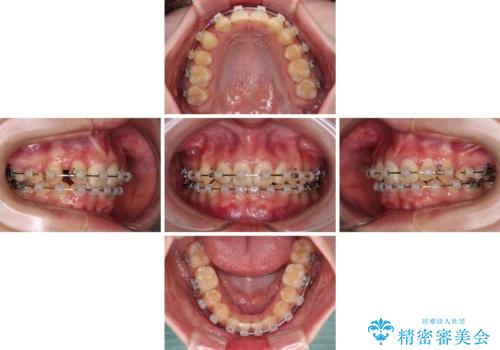

上顎左右第一小臼歯2本を抜歯し、ワイヤー装置にて矯正治療を行うこととしました。

通常の抜歯矯正と抜くべき歯の位置が異なるため、咬みにくさが残ってしまうのではないかと懸念されましたが、咬み合わせに違和感なく、スムーズに治療を終えることができました。